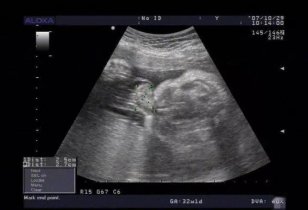

彩超的图像看起来还是黑白的,这正常吗

这是正常现象

做了假彩超吧

答案:这是正常现象

解析:彩超只有再看血管里面血流动方向的时候才表现为彩色,基本上屏幕全部都是黑白的,只有几个点是彩色的,所以并不是像彩色电视机那样全部都是彩色的,这是正常的。